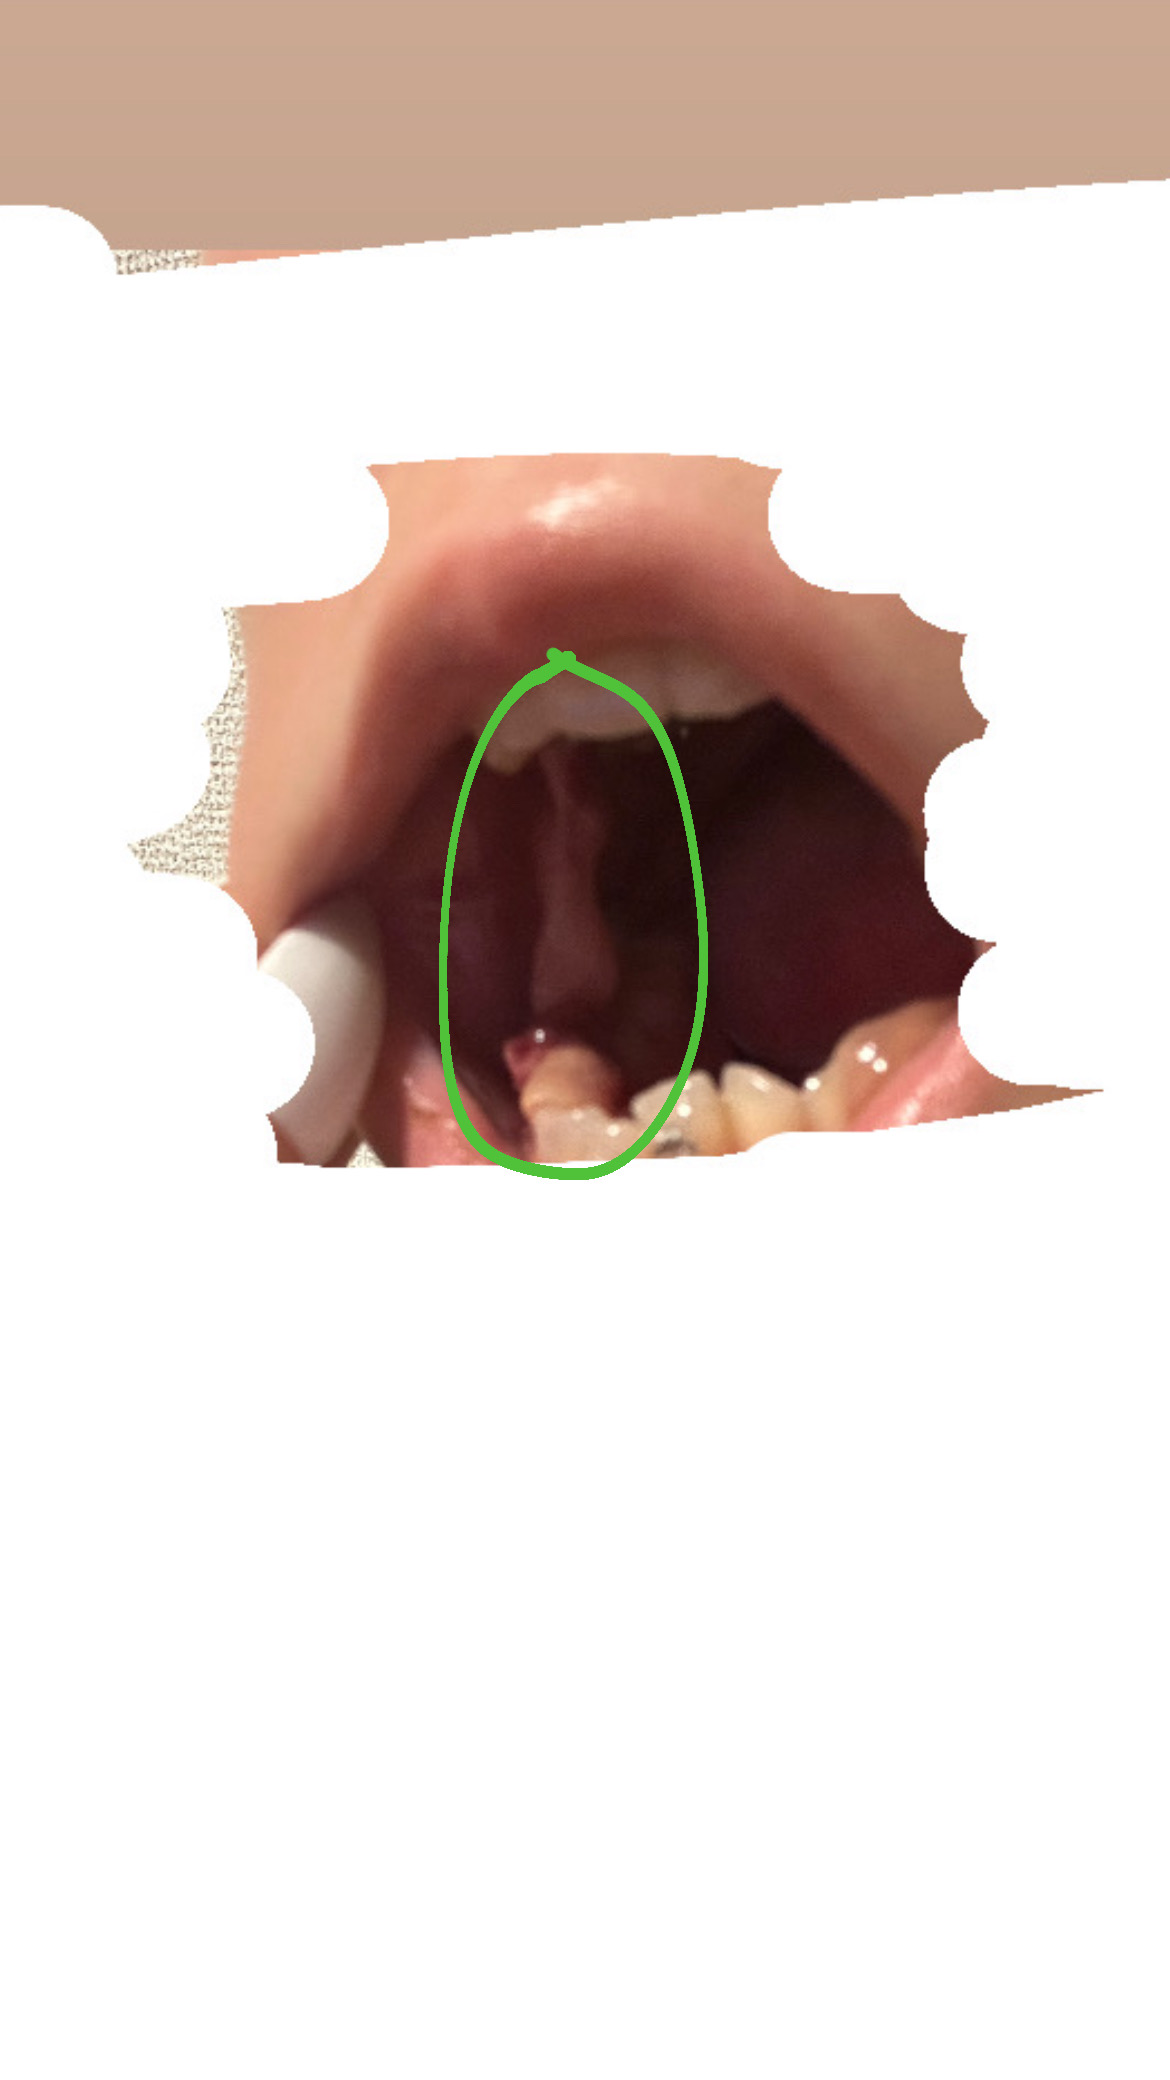

抜歯後の歯茎に突起物ができて痛みがあります。これは何ですか?

回答数:2 -